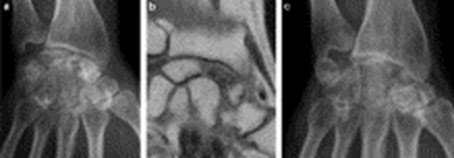

- Les clichés radiologiques standard du poignet, de face te de profil avec des clichés du côté sain pour comparer les deux images.

- Une IRM précisera l’étendue des lésions,

- Un arthroscanner précisera l’état de la structure osseuse et surtout l’état du cartilage du scaphoïde et du radius : ces deux éléments sont importants pour décider de l’option chirurgicale.

Stade I : image radiologique normale ; c’est un stade de début. L’IRM et la scintigraphie osseuse sont anormales.

Stade II : altérations de contraste dans le scaphoïde, prédominant au pôle proximal, près du radius : la forme du scaphoïde est conservée.

Stade III : perte de forme du scaphoïde qui quelques fois se fragmente ; la portion supérieure du scaphoïde est effondrée avec une image en coquille d’œuf, témoin d’une fracture.

Stade IV : effondrement important du scaphoïde, avec images d’arthrose du poignet entre le scaphoïde et le radius.